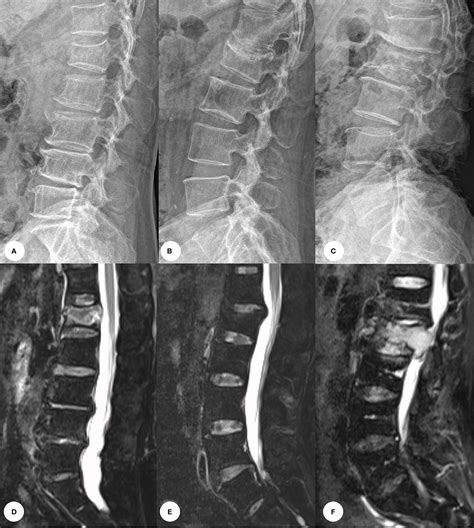

• Imaging Tests: X-rays are the primary tool for diagnosing fractures. In some cases, CT scans or MRIs may be used for more detailed images.

Imaging tests are crucial for understanding the acute fracture meaning and planning the appropriate treatment. X-rays provide clear images of the bone structure, helping to identify the type and severity of the fracture.